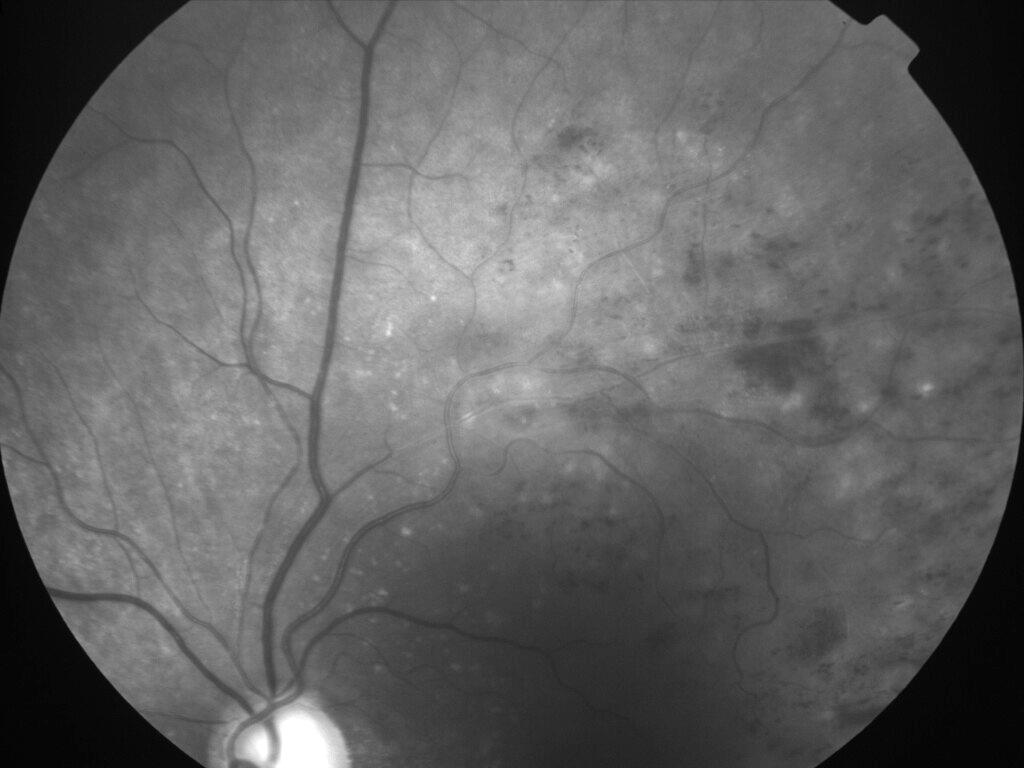

OCCLUSION DE BRANCHE DE LA VTS DE FORME ISCHEMIQUE MAJEURE